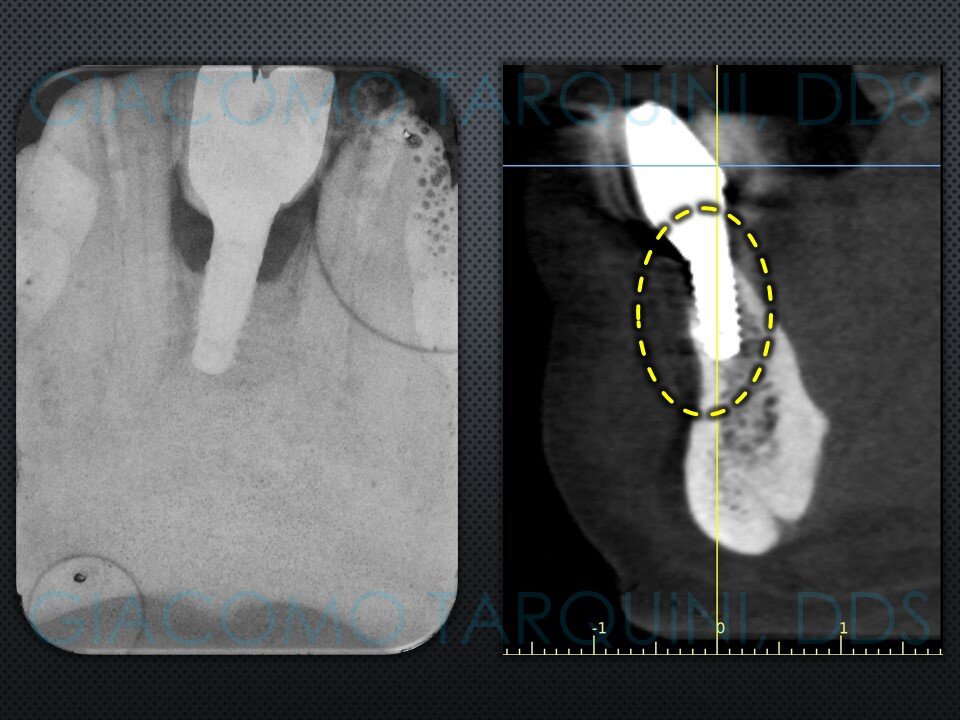

- Sondaggio e valutazione radiografica peri-implantare

- Rientro chirurgico e follow-up radiografico per valutare il grado di rigenerazione ossea ottenuta

Ho aggiornato il caso clinico con ricostruzione Panorex + sondaggi parodontali pre e post-operatori.